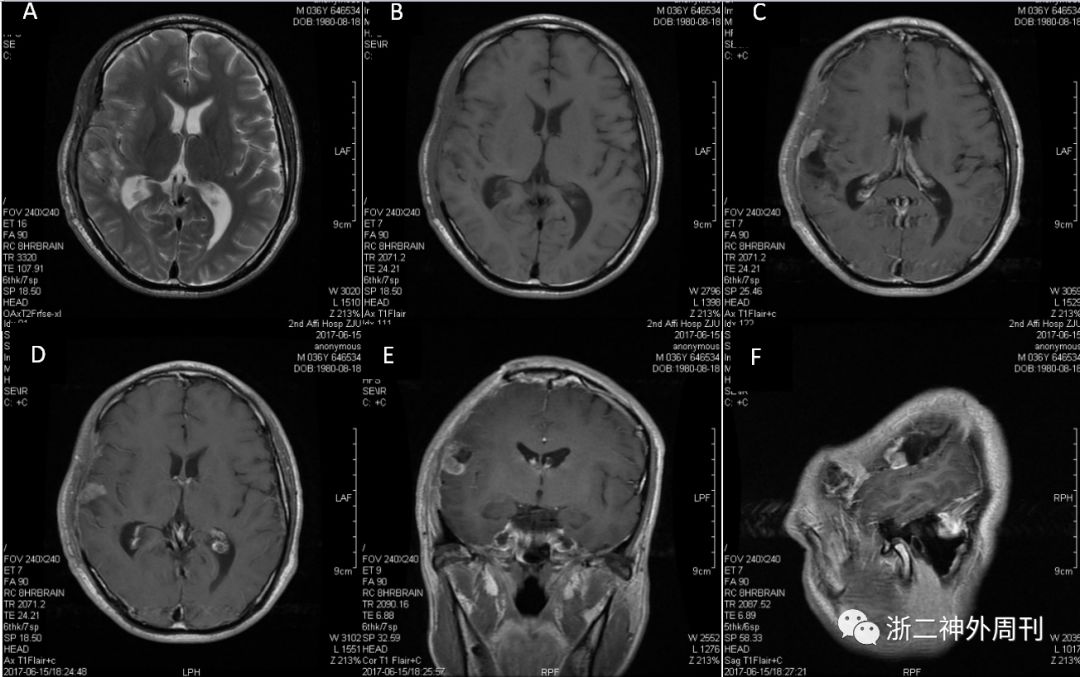

术后2个月当地医院复查MRI,提示右侧肿瘤术后改变,肿瘤部分残留。2017.6来浙医二院神经外科就诊,复查头颅MRI示:“病灶前缘见结节状,环形明显强化”(图2)。

图2.浙医二院头颅MRI示右侧额叶肿瘤术后,残腔边缘见异常强化。